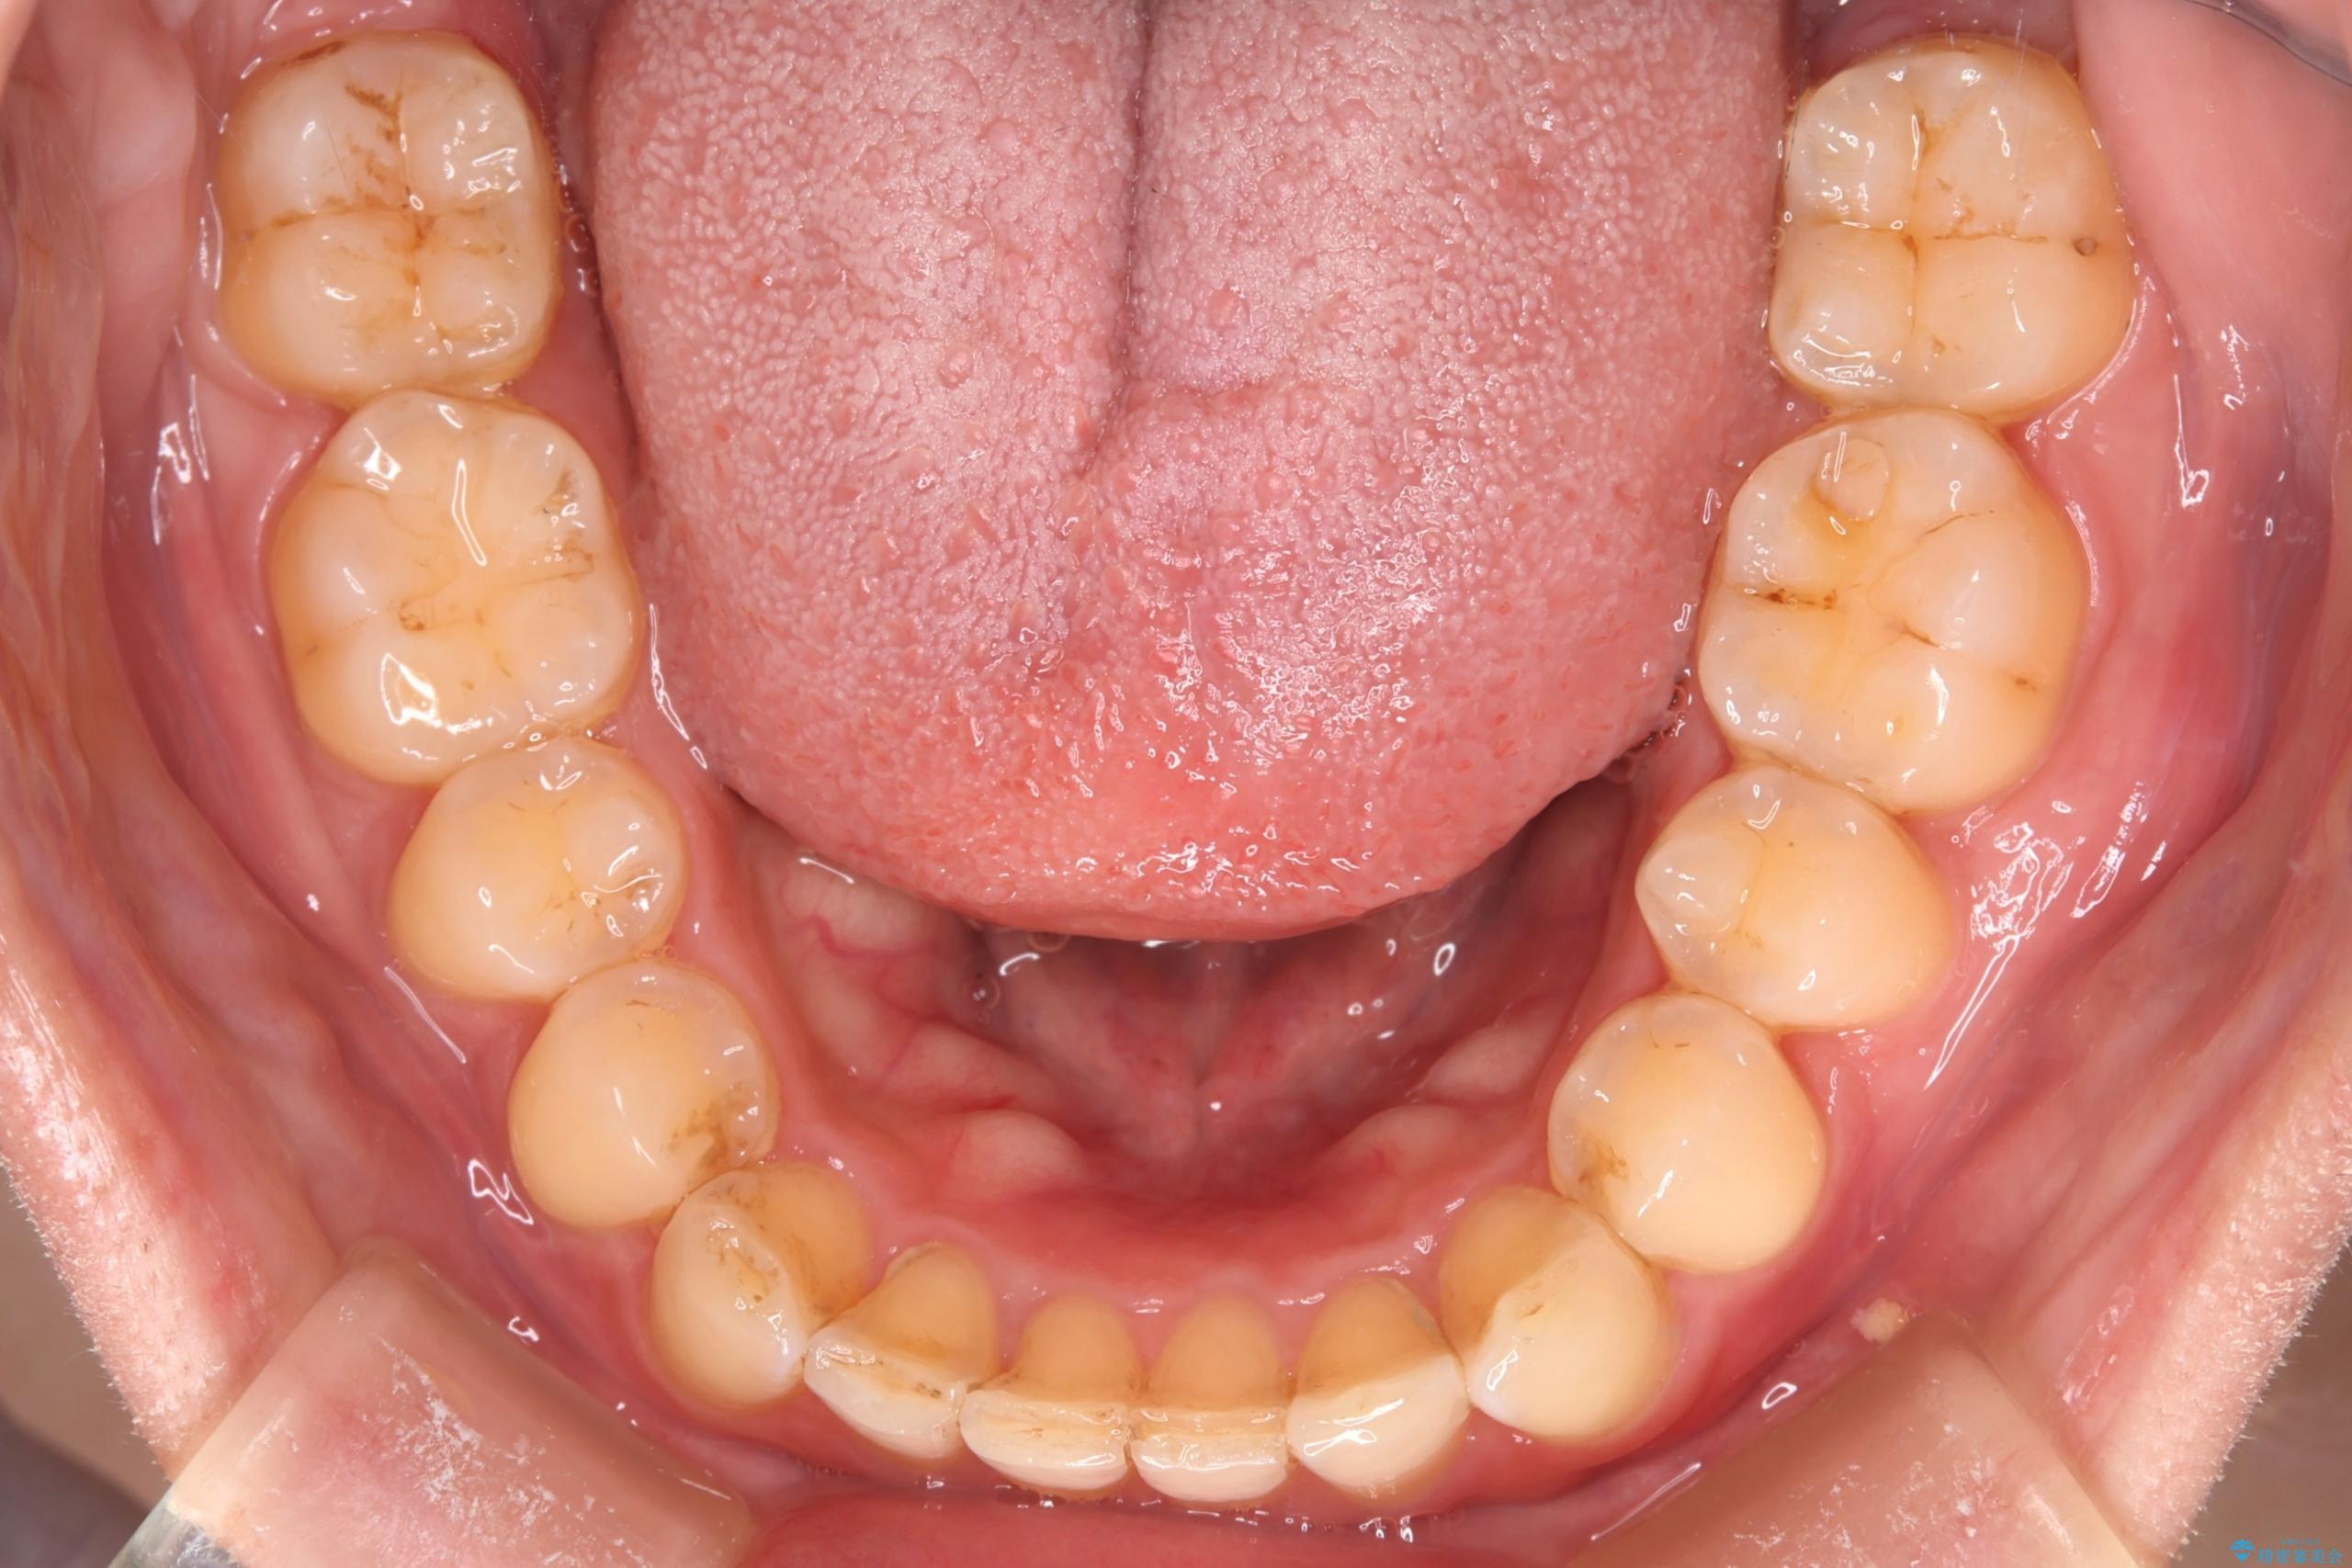

- 下の歯のがたつきを主訴に来院されました。

下の歯のがたつきと右の奥歯の噛みあわせ改善するために治療計画を立てることにしました。

下の前歯のがたつき改善にはIPR(歯と歯の間を削る処置)を行いました。